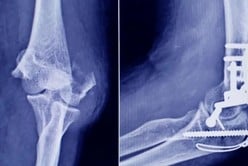

En paralelo a las inhibiciones a los laboratorios, la ANMAT dispuso la prohibición del uso, la comercialización y la distribución en todo el territorio nacional de dos unidades de un sistema de stent para prevención embólica de la carótida.

Los productos, debidamente identificados por número de serie y lote, están indicados para pacientes con alto riesgo de sufrir eventos adversos en procedimientos de revascularización carotídea.

La ANMAT explicó que, al desconocerse el estado de conservación y las condiciones en las que quedaron los stents tras el robo, no es posible garantizar su funcionalidad ni su seguridad, lo que representa un potencial riesgo para la salud de los pacientes.

Por este motivo, el organismo ordenó su prohibición preventiva e informó la medida a todas las autoridades sanitarias jurisdiccionales, con el objetivo de evitar que las unidades sustraídas puedan ser utilizadas o comercializadas de manera irregular